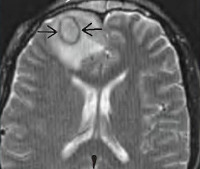

• Лучевые методы визуализации. Выполняется КТ лицевого скелета, КТ и МРТ головного мозга. Первая методика позволяет визуализировать горизонтальный уровень гнойных масс в околоносовых синусах, гнойное расплавление костных стенок их полостей. Магнитно-резонансная томография отображает воспалительные изменения мозговых оболочек, наличие абсцессов, их точную локализацию и размеры. КТ головного мозга с контрастным усилением при синустромбозе визуализирует дефект наполнения, общую деформацию и расширение полости синуса.